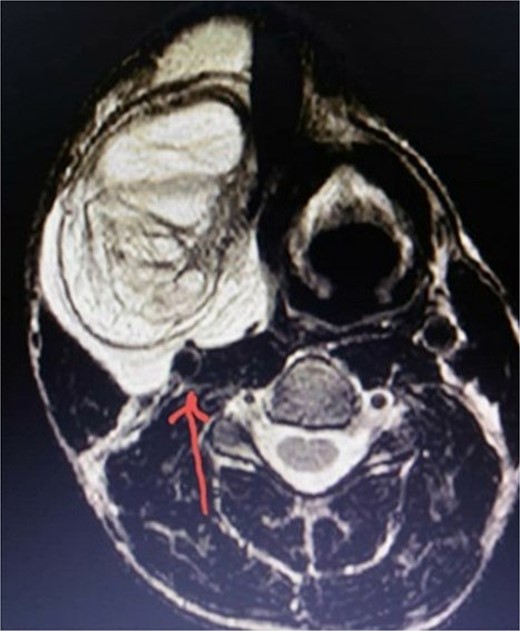

A neck ultrasound revealed a well-defined, solid, mildly hyper-echoic, heterogeneous subcutaneous mass located on the right side of the neck. A contrast-enhanced MRI scan showed a 14 cm diameter, well-demarcated, high-signal, non-homogeneous mass adjacent to the carotid artery and thyroid gland (Figs 1 and 2). The radiologist suggested lipoma as the most probable diagnosis. Ultrasound-guided fine-needle aspiration (FNA) of the mass identified some lipocytes and fibrocytes but no malignant cells.

T2-weighted MRI image showing the relationship between the mass and the carotid sheath (indicated by the arrow).